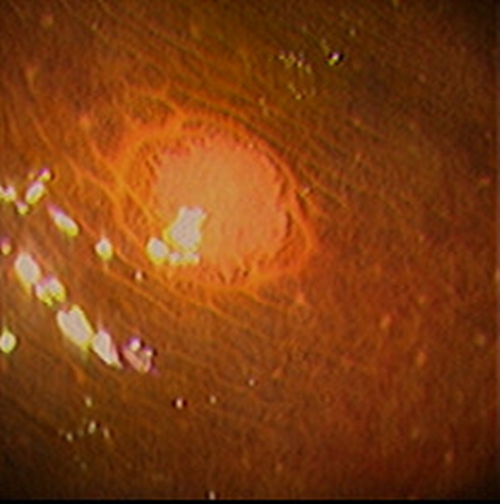

急性胃炎圖片

急性胃炎